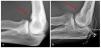

- Diagnóstico radiológico estándar: radiografías del codo en dos planos (fig.3).

Fig. 3 a, b) Vista general sobre el diagnóstico radiológico preoperatorio. En la radiografía estándar de la articulación del codo se observan cambios óseos, incongruencia articular, presencia de osteofitos y cuerpos libres articulares.